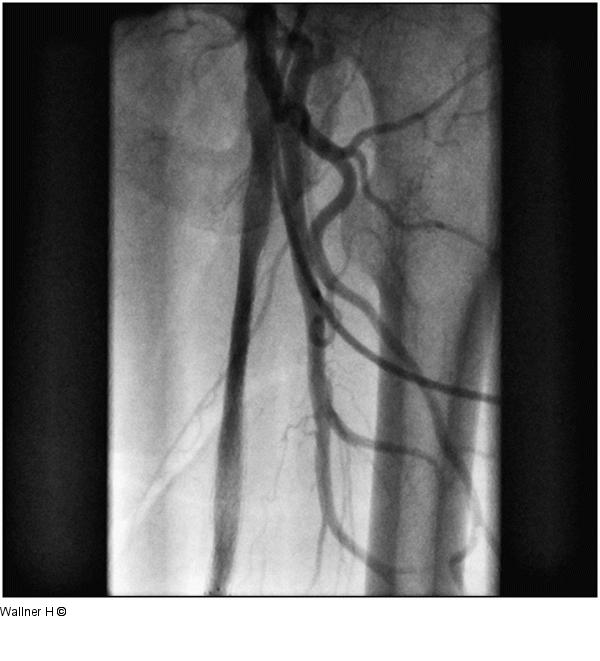

Abbildung 5: Perkutane transpopliteale retrograde Rekanalisation Wiedereröffnete A. femoralis communis nach Stentimplantation. |

Wiedereröffnete A. femoralis communis nach Stentimplantation. |